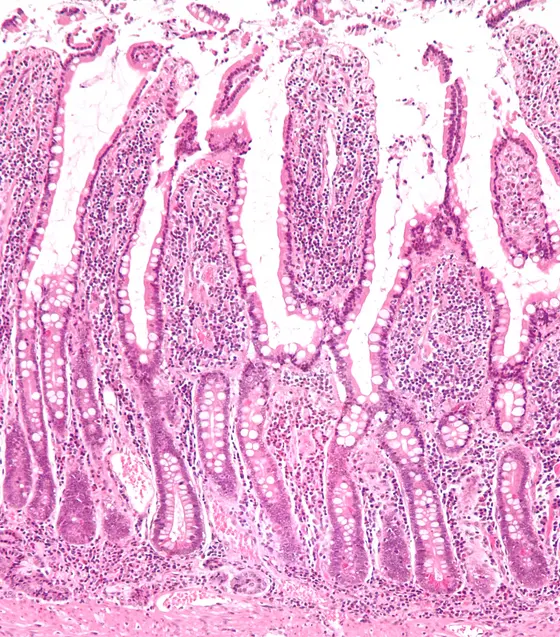

Intestinal stem cells are located deep at the bottom of the intestinal crypts.

The intestinal epithelium renews itself completely every four to seven days. Intestinal stem cells are responsible for this, constantly supplying the various types of specialized cells of the intestine. The stem cells are located at the base of tiny pits in the intestinal epithelium, known as crypts.